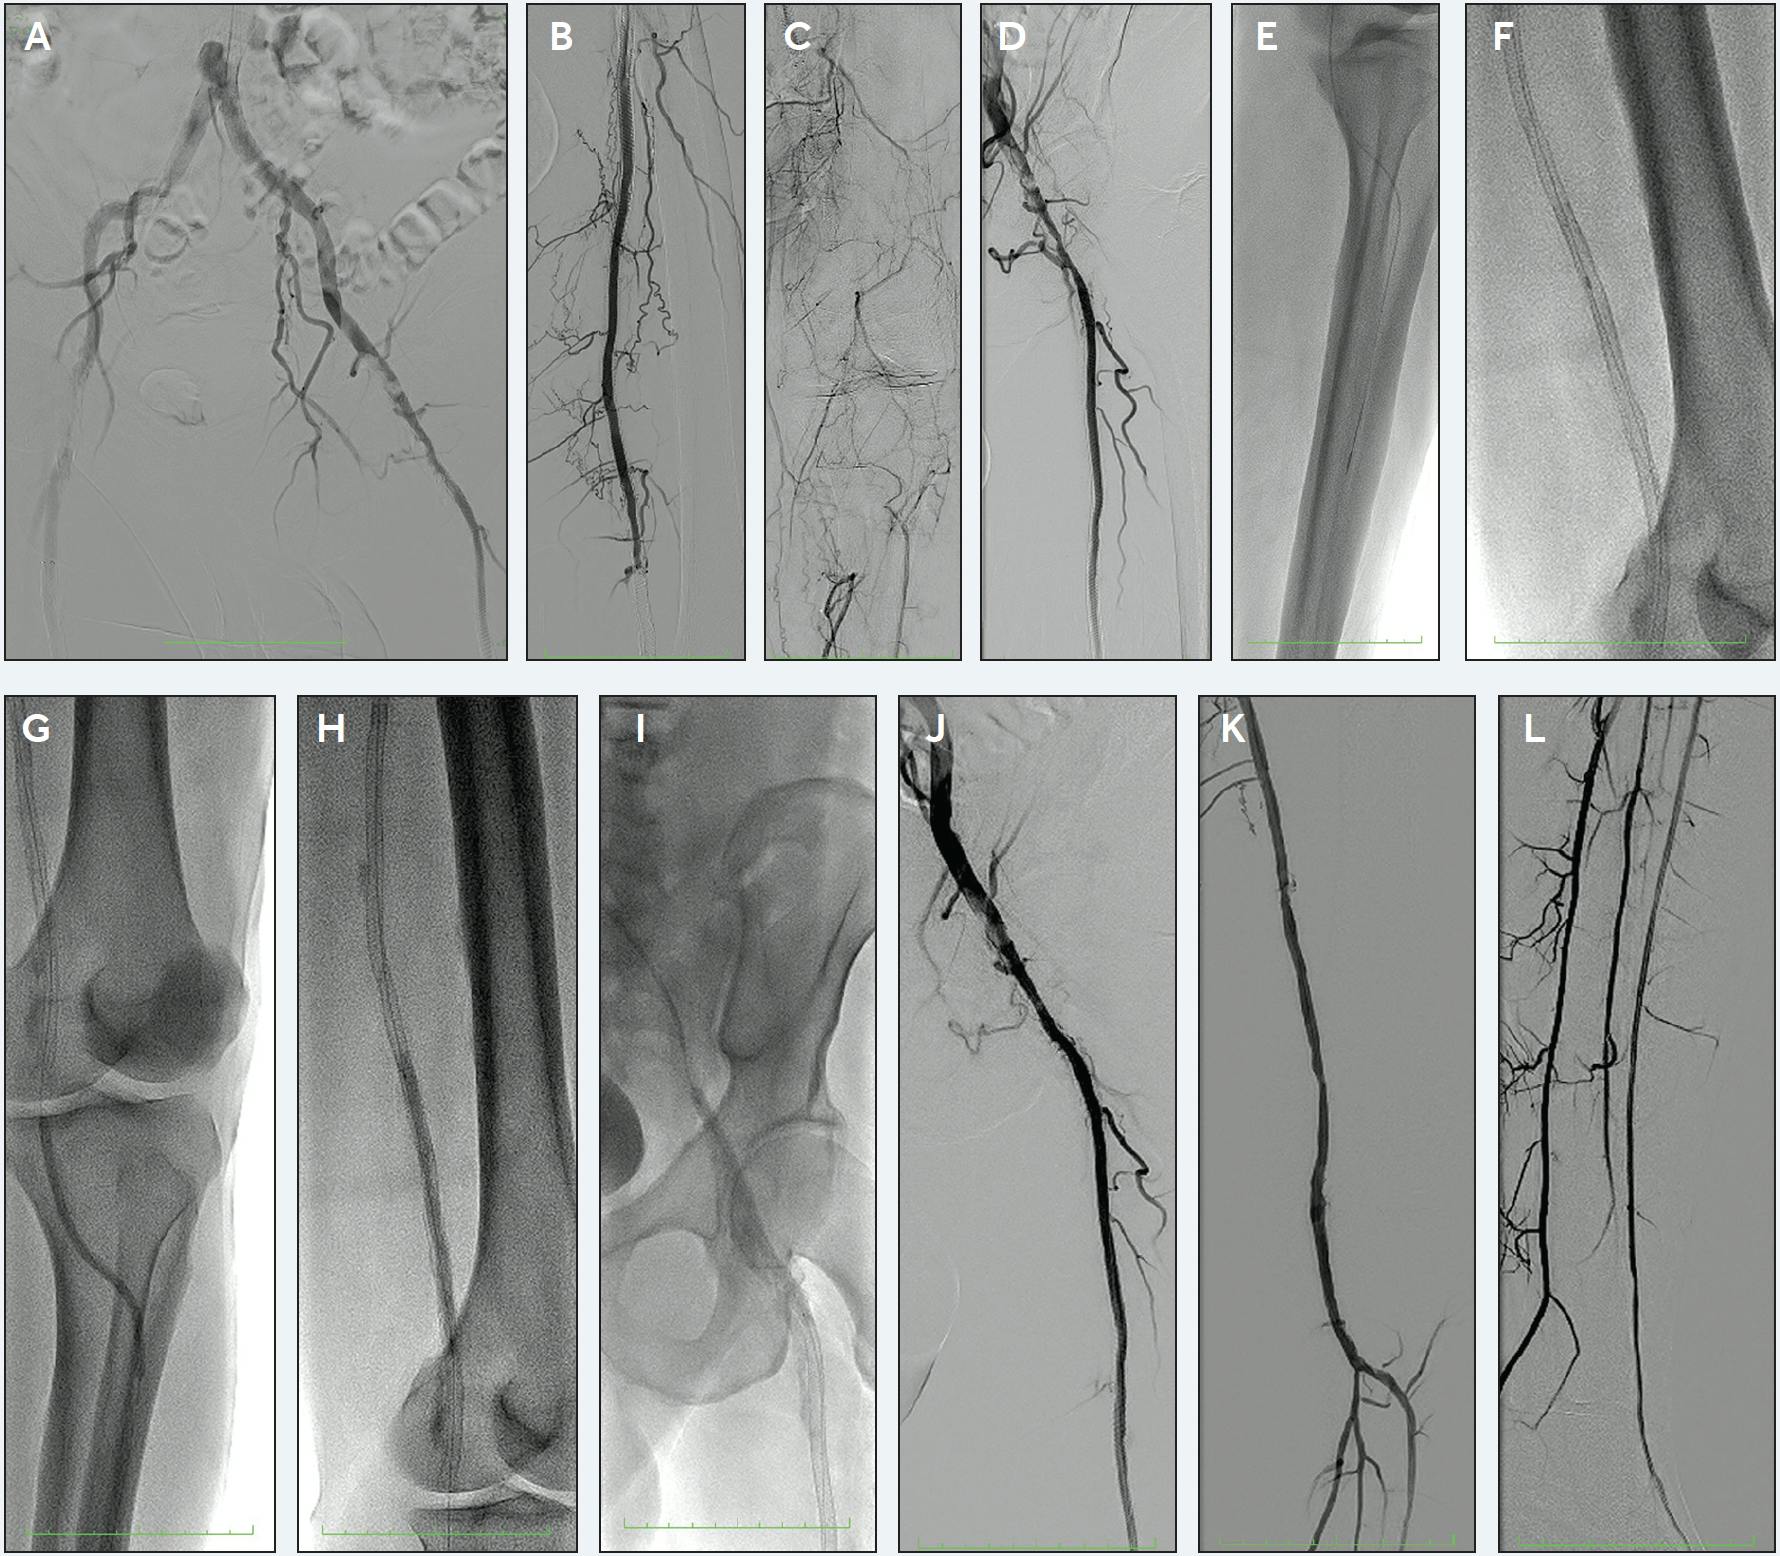

Under ultrasound guidance, the right radial artery was accessed, and a 6-F Glidesheath Slender hydrophilic sheath (Terumo Interventional Systems) was initially used for access. Diagnostic angiography was performed transradially that demonstrated severely calcified left CFA stenosis with over 30 mm Hg gradient noted through a 4-F diagnostic catheter (Figure 1A). As suggested by the duplex ultrasound, the distal left SFA and PA stented region was occluded, with profunda femoris and geniculate collaterals reconstituting the AT and posterior tibial arteries distally (Figure 1B-1D). A 119-cm R2P Destination Slender sheath (Terumo Interventional Systems) was used for the intervention with unfractionated heparin used for procedural anticoagulation. The patient continued his dual antiplatelet therapy periprocedurally per his routine dose and schedule.

Figure 1. Transradial abdominal aortography demonstrating severely calcified bilateral CFA stenosis (A). Left lower extremity angiography demonstrating occlusion of the distally stented segment in the left SFA (B). Left lower extremity angiography demonstrating long-segment occlusion involving the entire PA and proximal tibial vessels (C). Left lower extremity angiography demonstrating severely calcified eccentric left CFA stenosis (D). Angiogram demonstrating crossing of CTO into the left AT artery (E). Auryon XL 1.5-mm laser catheter being used to treat the area of CTO from the distal SFA into the AT artery (F). 4-mm balloon angioplasty of the distal left PA extending into the AT artery (G). 6-mm noncompliant balloon angioplasty of the distal left SFA and PA (H). 7-mm noncompliant balloon angioplasty of the left CFA (I). Left lower extremity angiography of left CFA after Auryon XL 1.5-mm laser atherectomy at 60 mJ/mm2 and angioplasty (J). Left lower extremity angiography of left SFA and PA after Auryon XL 1.5-mm laser atherectomy at 60 mJ/mm2 and angioplasty (K). Left lower extremity angiography of left AT artery after Auryon XL 1.5-mm laser atherectomy at 50 mJ/mm2 and angioplasty demonstrating resumption of brisk three-vessel runoff (L). Actual procedure results/images. Images courtesy of Dr. Amit Srivastava. These images and results represent the experience of one institution and are not indicative of all procedure results.

A 0.035-inch Glidewire Advantage and R2P NaviCross catheter (both from Terumo Interventional Systems) were used to cross the left SFA and PA total occlusions into the left AT artery (Figure 1E). A radial-length ViperWire (Abbott) was advanced in a prolapsed fashion into the dorsum of the left foot. A 1.5-mm Auryon XL 225-cm-long catheter (AngioDynamics, Inc.) was used to treat the calcific left CFA for 2 minutes and 30 seconds at 60 mJ/mm2 as well as the occluded distal left SFA and PA for 2 minutes and 30 seconds at 60 mJ/mm2. The most distal left PA extending into the left AT artery was treated with this same catheter at 50 mJ/mm2 for 5 minutes (Figure 1F). The distal left PA extending to the left AT artery subsequently underwent angioplasty with a 4-mm semicompliant Crosstella balloon (Terumo Interventional Systems) (Figure 1G). The left SFA and proximal to mid PA occluded segments underwent angioplasty with a 6-mm Jade noncompliant balloon (Abbott) (Figure 1H). The left CFA was treated with angioplasty using a 7-mm Jade noncompliant balloon (Figure 1I). All angioplasty was performed at nominal pressure for 3-minute inflations.

Postintervention, a marked angiographic appearance and no residual pressure gradient were noted in the left CFA (Figure 1J). Brisk three-vessel runoff with no residual pressure gradient was also noted in the areas of distal intervention (Figure 1K and 1L).